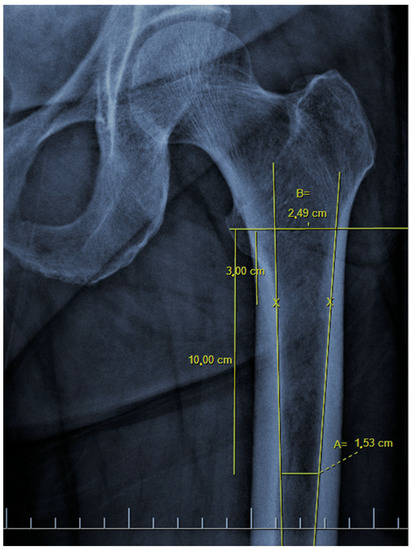

There are also osteoporosis measurements that can be detected by direct radiography, such as the Singh index, Dorr index, cortical thickness index, and canal-to-calcar isthmus ratio. The Singh Index (SI) is a method of measuring osteoporosis determined by detecting trabecular patterns in the proximal femur with plain radiographs. According to the Singh index, osteoporosis is divided into six grades (Grades 1–6). As the grade progresses, the level of osteoporosis decreases; grades 1–3 define definitive osteoporosis (Figure 1) [8]. The Dorr index (DI) is divided into three types according to cortical thickness on proximal femur radiographs (Types A-B-C). As the type progresses, the level of osteoporosis increases (Figure 2) [9,10]. The cortical thickness index (CTI) is measured 10 cm distal to the trochanter minor; its decrease indicates that the cortex is thinning, thus increasing osteoporosis (Figure 3) [9,10]. The canal-to-calcar isthmus ratio (CCR) is calculated as the ratio of the canal diameter 10 cm distal to the trochanter minor to the canal diameter at the calcar on plain radiographs. An increase in this ratio indicates an increase in osteoporosis (Figure 4) [9,10].

Figure 1. Singh index consists of six grades. In grade six, all trabecular patterns are visible and of normal thickness. In grade five, Ward’s triangle is prominent, and the principal tensile and principal compressive trabeculae are easily visible. In grade four, the principal tensile trabeculae are continuous but thinned. In grade three, loss of continuity is accompanied by thinning of the principle tensile trabeculae. In grade two, except for the principal compression trabeculae, the trabeculae are almost invisible. In grade one, principal compressive trabeculae are visible as thin. Antero-posterior hip radiograph of a patient with Singh grade 6 is shown.